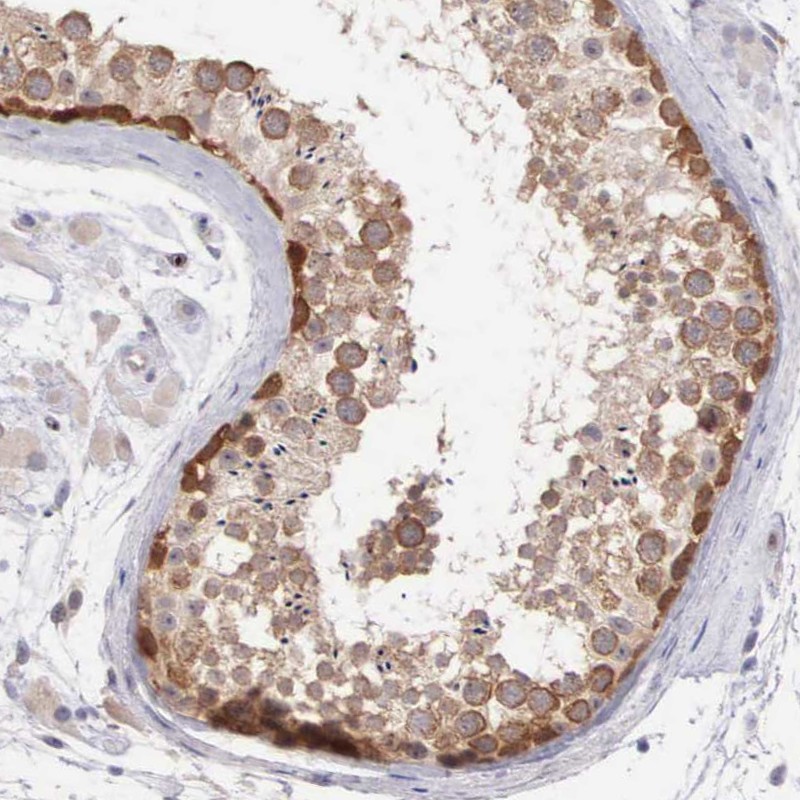

Immunohistochemical staining of human testis shows strong cytoplasmic and positivity in cells of seminiferous ducts.